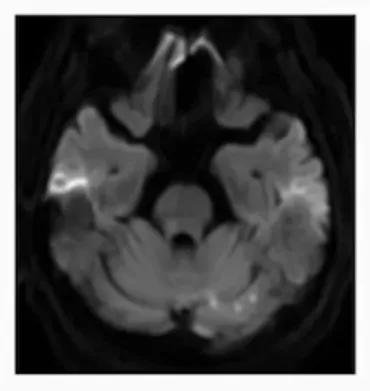

★ 左椎动脉、基底动脉狭窄